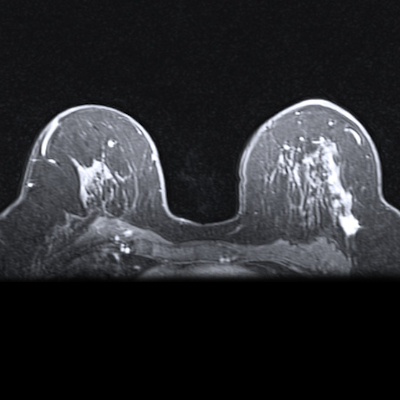

Images show breast cancer in two women at baseline multiparametric MRI. (A) Image shows axial delayed-phase dynamic contrast-enhanced MRI scan in a 51-year-old woman with luminal B no special type carcinoma in the left breast 240 seconds after gadolinium chelate injection. (B) Image shows axial T2-weighted image in the same woman as in (A). At core biopsy, the lesion was considered as HER2 low. The lesion was correctly classified by the radiomic signature (0.87 ≥ threshold). (C) Image shows axial delayed-phase dynamic contrast-enhanced MRI scan in a 43-year-old woman with luminal B no special type carcinoma in the right breast 240 seconds after gadolinium chelate injection. (D) Image shows axial T2-weighted image in the same woman as in (C). At core biopsy, the lesion was considered as HER2 zero. The lesion was correctly classified by the radiomic signature (0.45 < threshold). Images and caption courtesy of the RSNA.The training set included 208 women with an average age of 53 years from one center, while the external test set included 131 patients with an average age of 54 years from a second center.